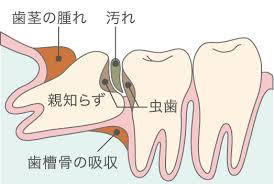

親知らずが痛くなる原因はいくつかあります。①親知らず自体が虫歯になる。②親知らずが歯肉を噛み込んでしまう。③親知らずの周りが汚れて炎症がおきる。いちばん多いのが③です。①は他の歯と同様に親知らずも虫歯になります。磨きにくい歯ですので虫歯になるリスクも高いので注意が必要です。②は、親知らずは全てが生えてくるわけではありません。近年は、人の顎は小さくなってきています。その結果、親知らずが十分に生えるスペースがないことがあります。上の親知らずだけが生え、下の親知らずは、歯肉に埋まったままのことがあります。すると、上の歯で下の歯肉を噛んでしまい、痛みがでます。

親知らずの周りの炎症

いちばん多いのが、親知らず周りの炎症です。生えるスペースの減少により、親知らずが完全にでてこれなくて、半分もしくは、一部分だけ見えている事があります。歯ブラシがうまくあてられず、汚れがたまり歯の周辺が炎症を起こします。これが、智歯周囲炎とよばれ、親知らずが痛む多くの原因です。